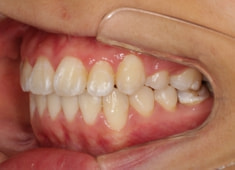

治療後(2年後)